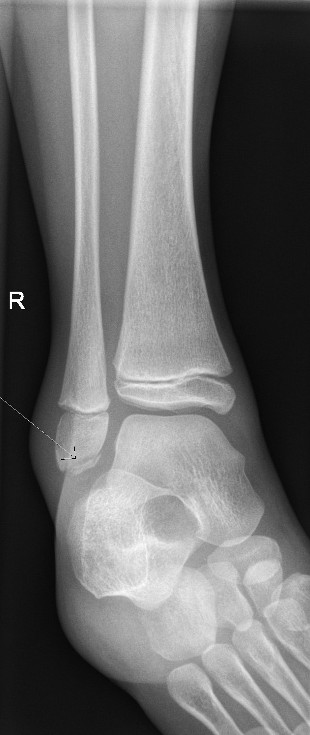

Minimally displaced Salter-Harris II fracture of distal fibula

Salter Harris II Fractures

- If undisplaced, manage in a CAM boot for 3-4 weeks weight bearing as tolerated with GP follow up for a repeat X-ray in 7-10 days to ensure no displacement.

- If displaced, manage in a below knee plaster backslab, non-weight bearing with crutches and follow up in Orthopaedic Fracture clinic in 7-10 days.